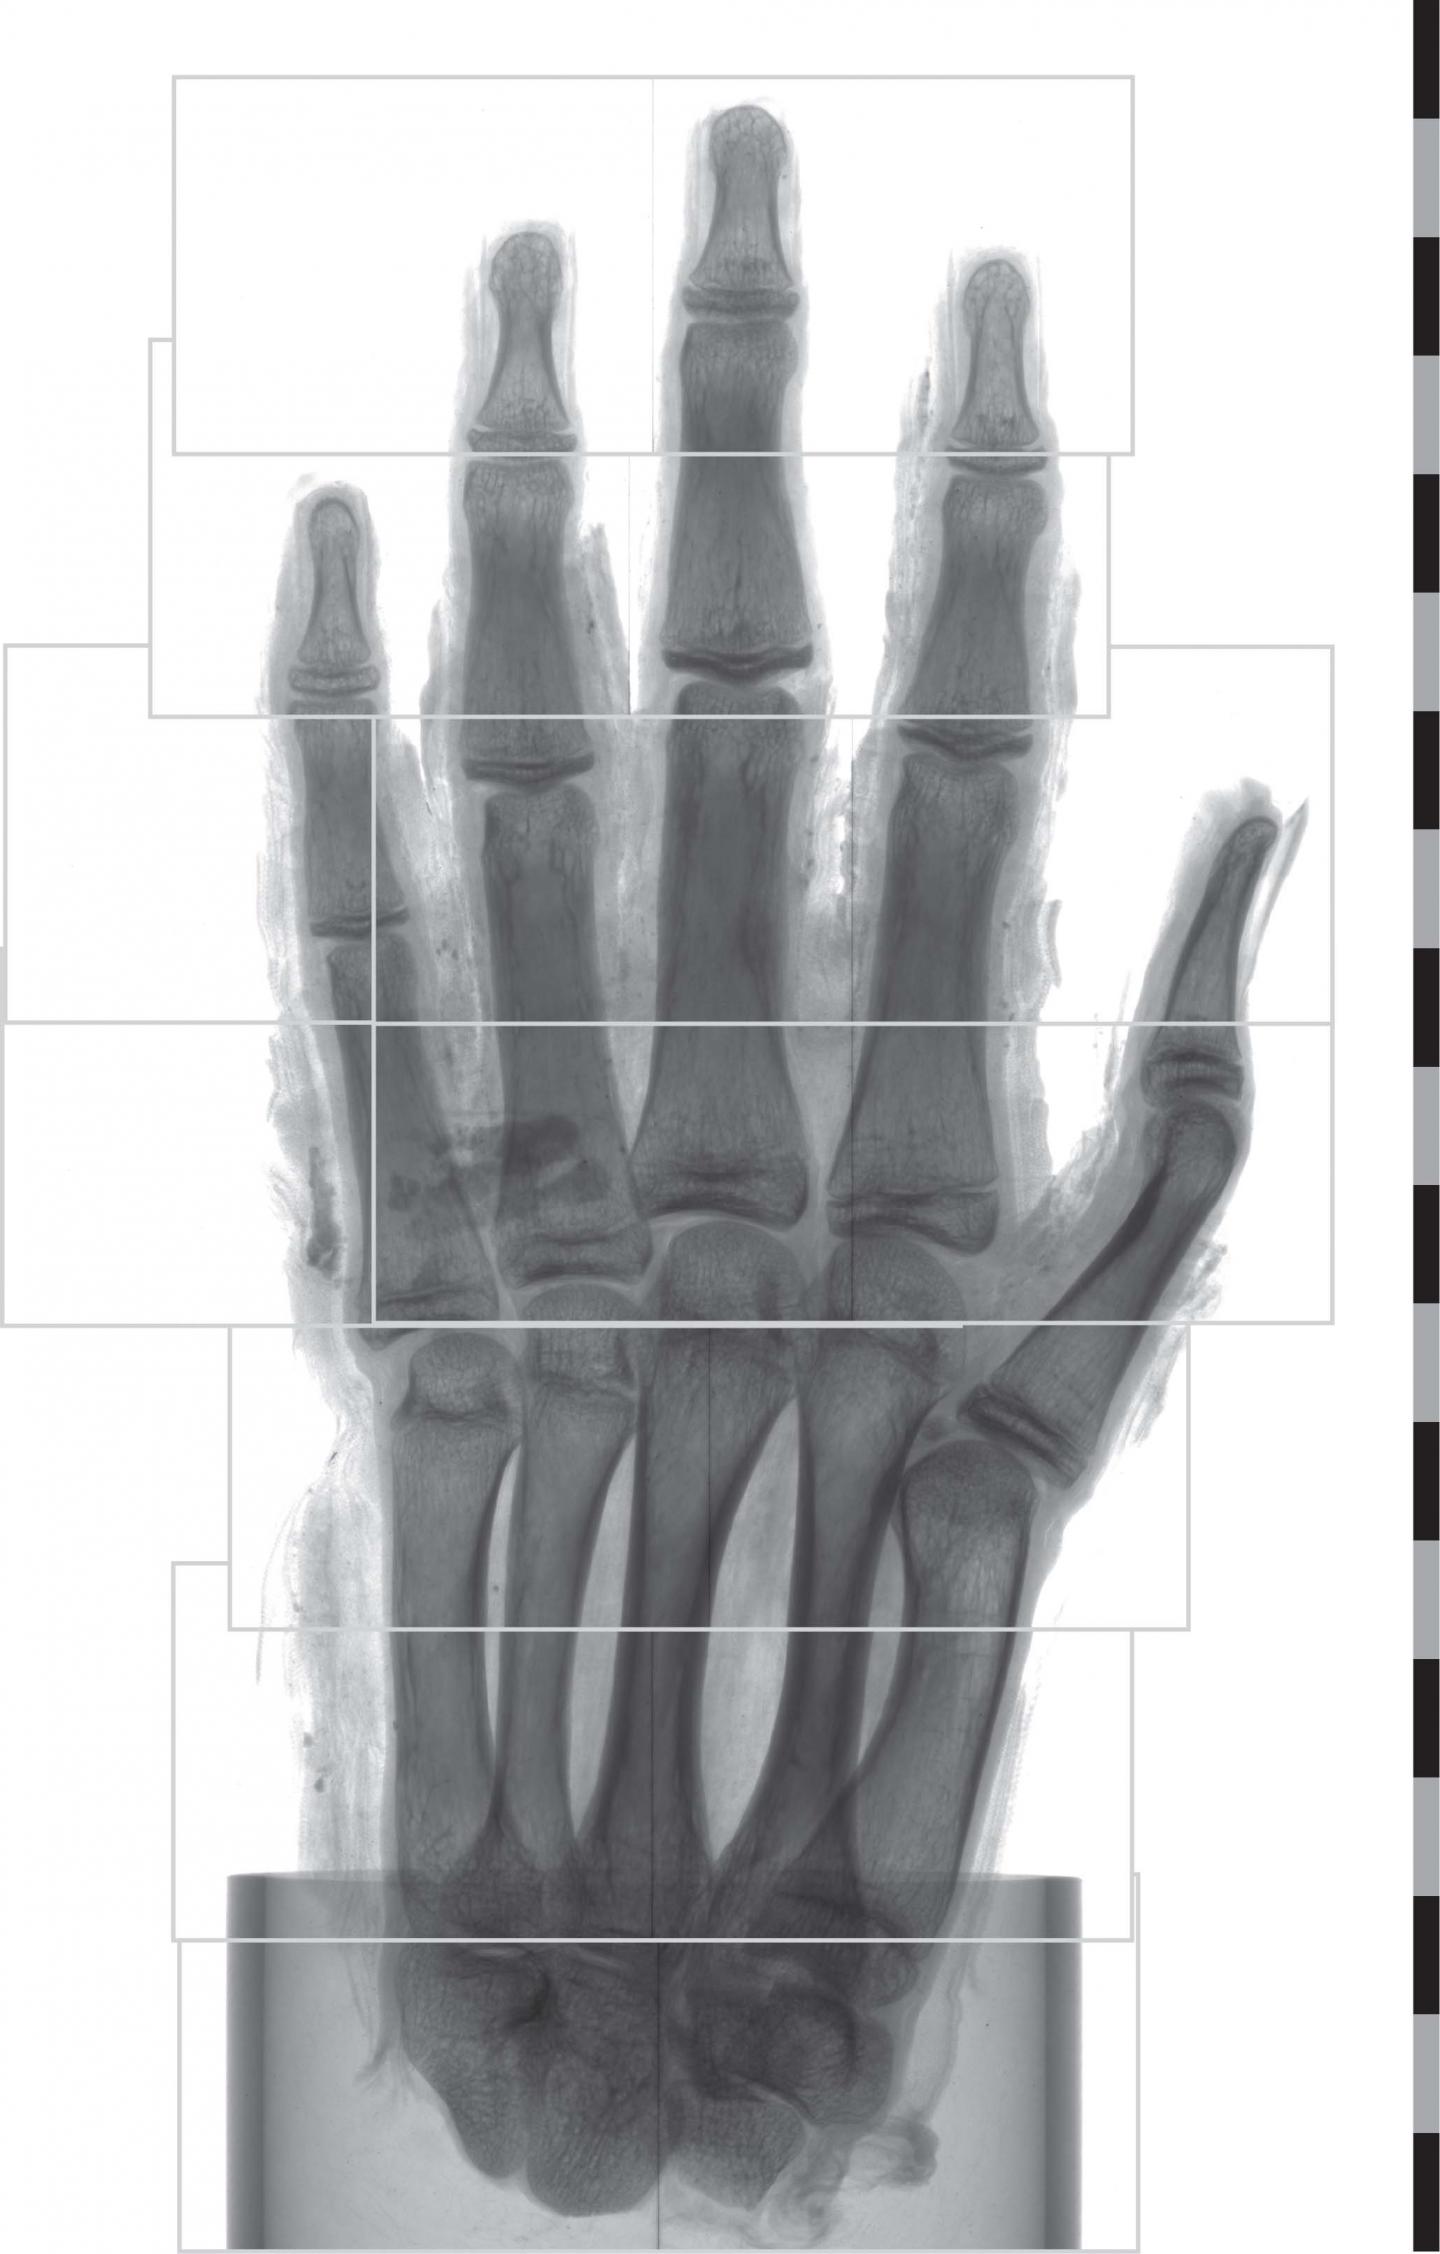

OAK BROOK, Ill. - Researchers in Sweden using computed tomography (CT) have successfully imaged the soft tissue of an ancient Egyptian mummy's hand down to a microscopic level, according to a study published in the journal Radiology .

Romell and colleagues evaluated phase-contrast CT by imaging a mummified human right hand from ancient Egypt. The hand, today in the collection of the Museum of Mediterranean and Near Eastern Antiquities, was brought to Sweden at the end of the 19th century, along with other mummified body parts and a fragment of mummy cartonnage (papier-mâché case). The cartonnage belonged to an Egyptian man and has been dated to around 400 BCE (before common era). They scanned the entire hand and then performed a detailed scan of the tip of the middle finger.

The estimated resolution of the final images was between 6 to 9 micrometers, or slightly more than the width of a human red blood cell. Researchers were able to see the remains of adipose cells, blood vessels and nerves; they were even able to detect blood vessels in the nail bed and distinguish the different layers of the skin.